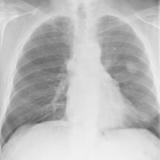

Thymoma

Date: 11/06/2013

Views: 3818